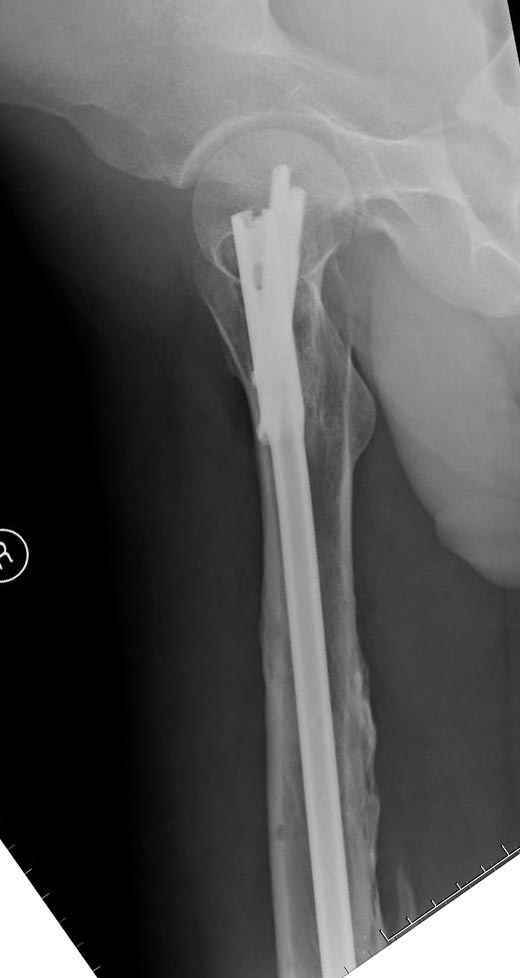

Мы не дождались “Happy End”, у больного IQ в пределах 70%, через 6 месяцев вернулся после небольшой травмы, споткнувшись получил перелом

того же бедра (рис №7).

При обзоре причин перелома, на снимке №2 обнаружили, что один из стержней аппарата наружной фиксации проходил только через передний кортекальный слой, что создало стрессовую зону на бедре и в результате перелом из-за незначительной травмы.

Снимок №4 сделан после несостоятельности интрамедуллярного штифта, осложнения инфекцией канала и после миграции шурупов. Я имел ввиду, что снимок № 2 после удаления наружного фиксатора в интрамедуллярном варианте, на увеличенном снимке дырка на переднем кортексе (см. снимок) stress zone Чтобы правильно без осложнений провести half pins, необходимо соблюсти нескольких правил, во первых, они должны вводится в середине диаметра кости с предварительным просверливанием. Во время просверливания кости, сверло проходит первый, потом второй дальний кортекс и стержен вводится вручную. А иногда сверление проходит по касательной к кортексу, нагреваются местные ткани, создается ожог и локальный некроз. Или как будто делается кортикотомия с помощью сверла, как при

методе Илизарова, ослабляя кортикальный слой. Создается стрессовая зона, которая при незначительной травме может осложниться стрессовым

переломом.